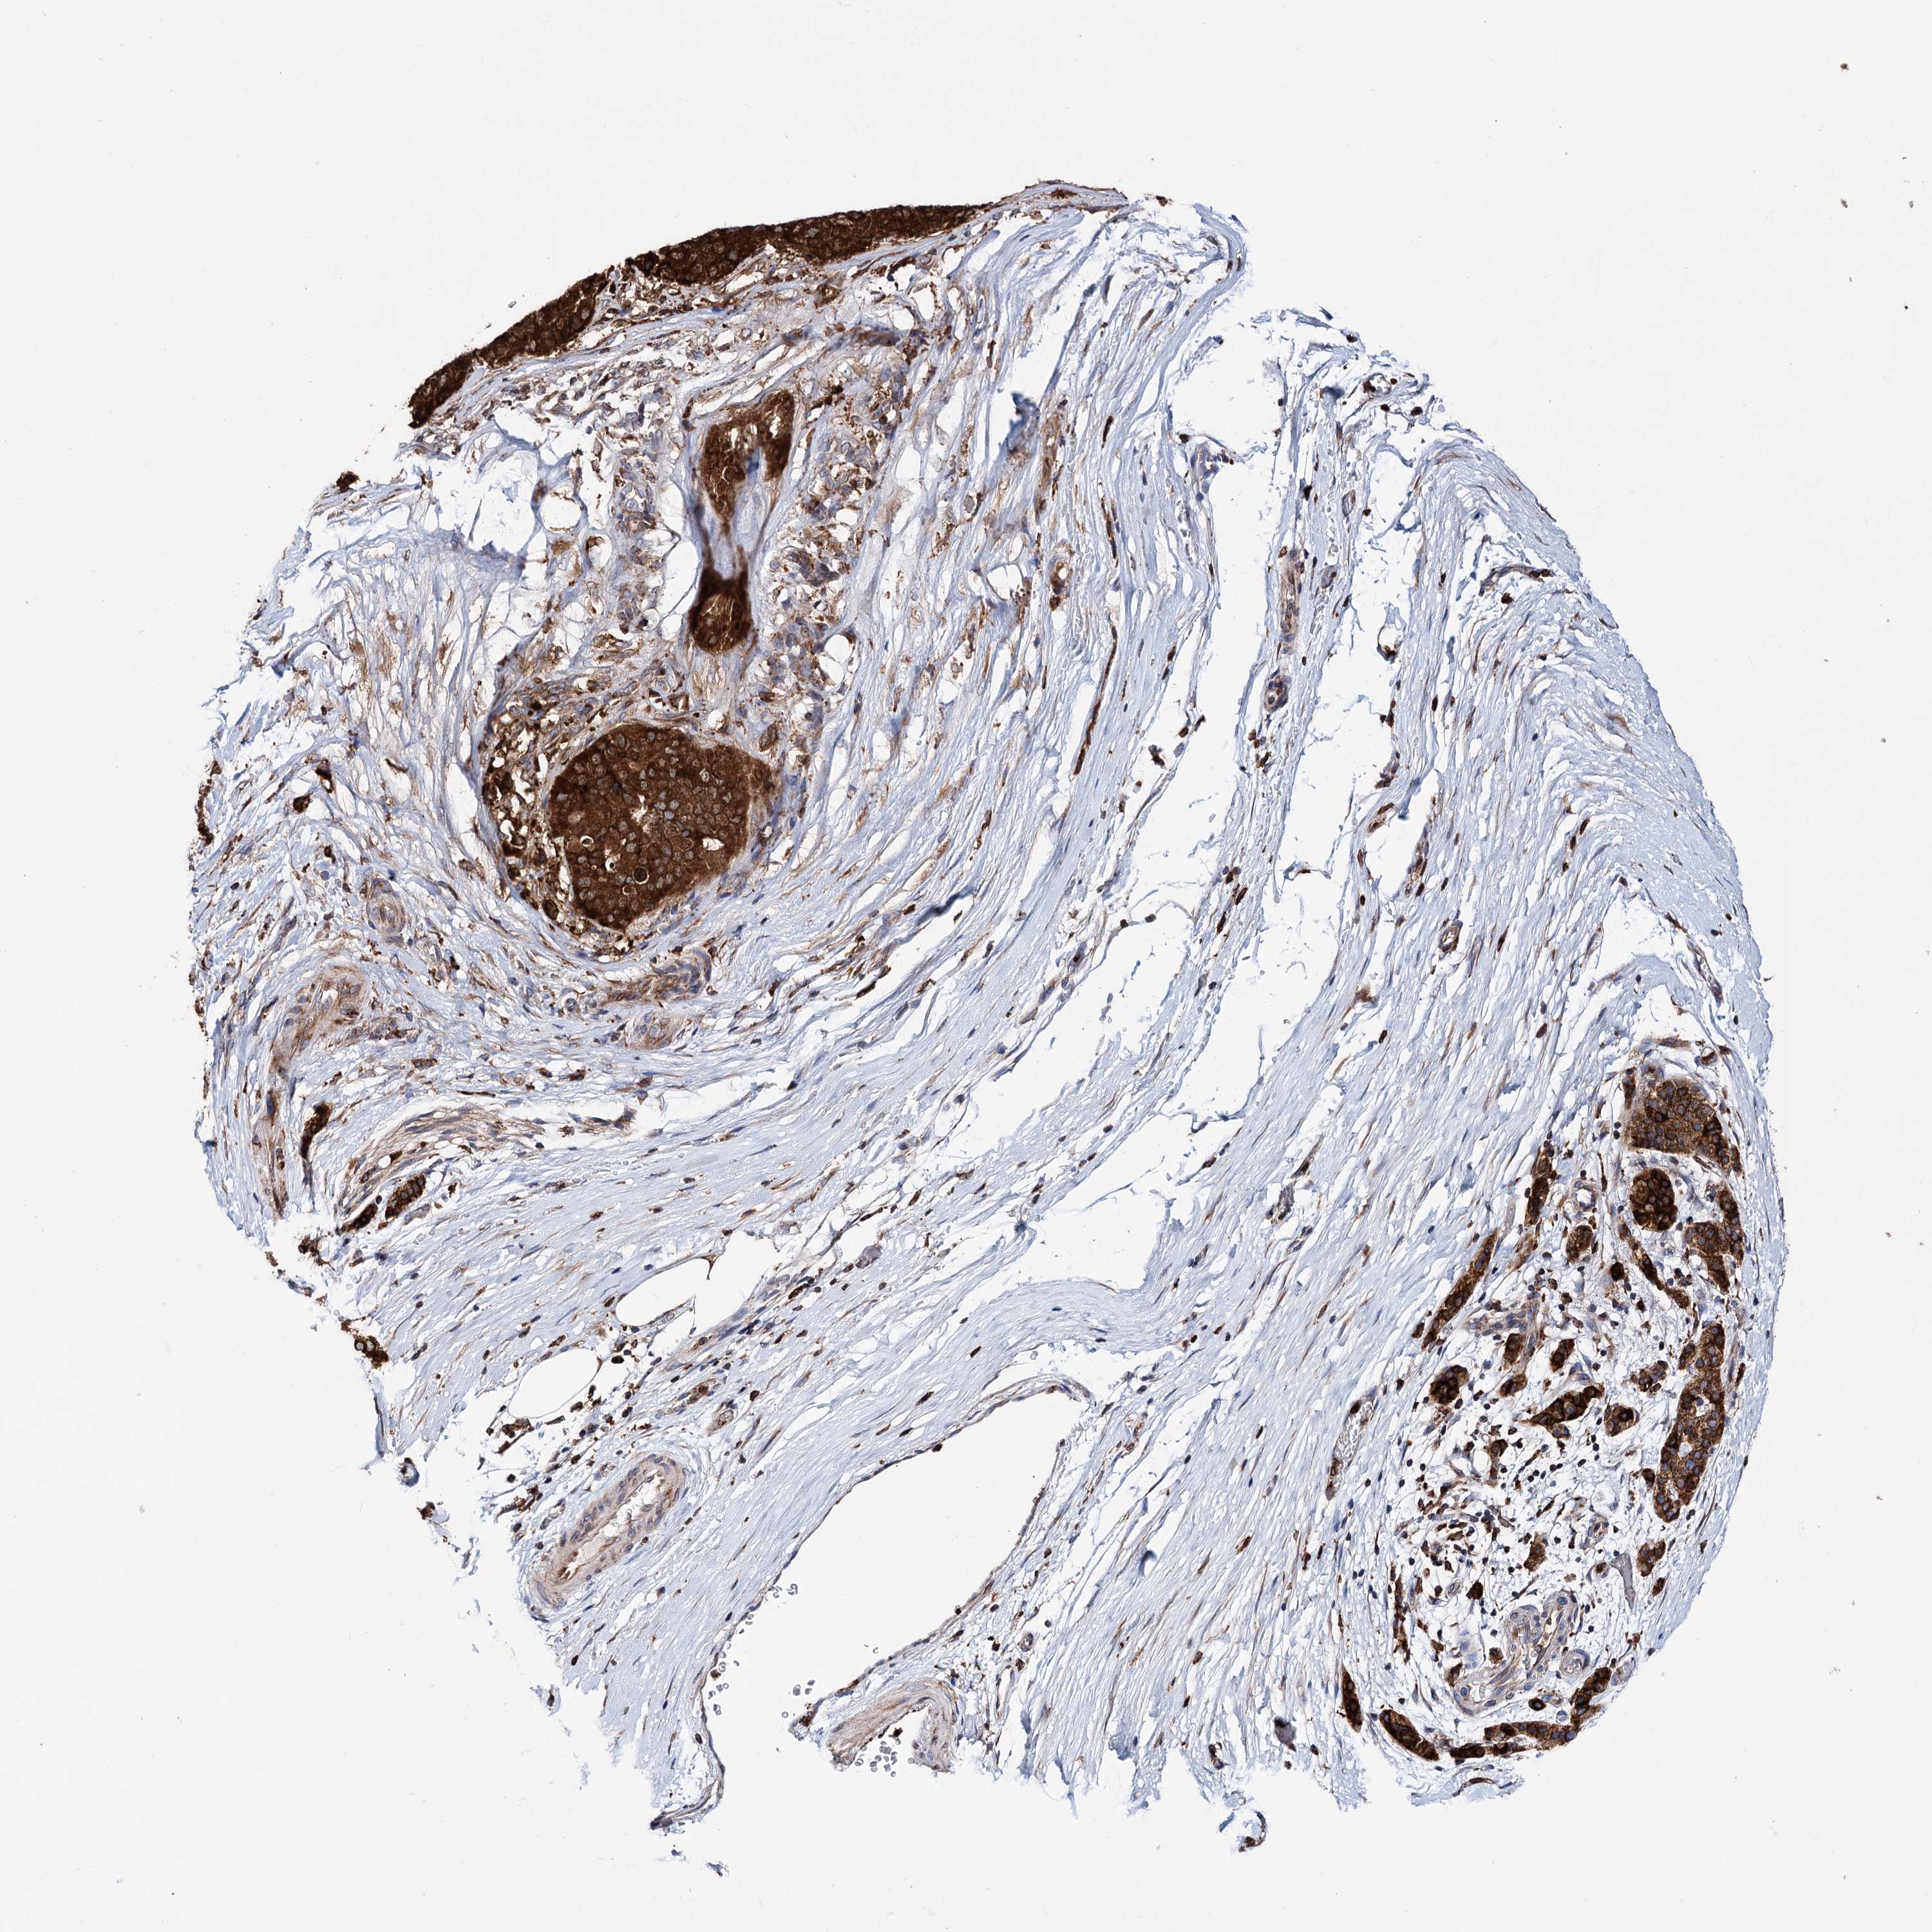

PANCREATIC CANCER - Protein expressioni

A mouse-over function shows sample information and annotation data. Click on an image to view it in a full screen mode. Samples can be filtered based on level of antibody staining by selecting one or several of the following categories: high, medium, low and not detected. The assay and annotation is described here.

Note that samples used for immunohistochemistry by the Human Protein Atlas do not correspond to samples in the TCGA dataset.

Antibody stainingi

Antibody staining in the annotated cell types in the current human tissue is reported as not detected, low, medium, or high, based on conventional immunohistochemistry profiling in selected tissues. This score is based on the combination of the staining intensity and fraction of stained cells.

Each image is clickable and will lead to virtual microscopy that enables deeper exploration of all samples and also displays staining intensity scores, fraction scores and subcellular localization as well as patient and tissue information for each sample.

Antibody HPA039363

Antibody HPA039456

Adenocarcinoma, NOS